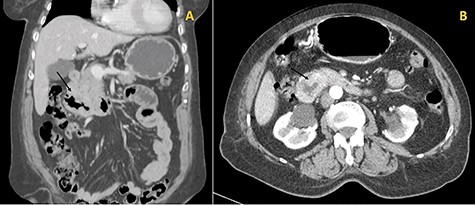

The histologic examination revealed a poorly differentiated adenocarcinoma, with a negative CDX2 and positive PAX8 immunostaining, hence compatible with a secondary lesion of endometrial origin (Figs 3 and 4).

Immunostaining positive for PAX8 suggesting a tumour of gynaecologic origin based on the patient’s past medical history.

To this day, despite direct invasion being quite common, there have been very few reports of duodenal metastasis of malignancies originated in distant organs. Lung, renal, melanoma and colorectal cancer have sporadic reports of duodenal involvement [8, 9]. When identified on endoscopy, they frequently present as ulcerated lesions that can cause GI bleeding or gastric outlet obstruction. This finding is consistent with the endoscopy’s macroscopic description of the duodenal lesion and our patient’s clinical presentation. Immunohistochemistry provided the diagnosis after confirming its non-lower GI tract origin and gynaecologic related epithelial structure (positive for cytokeratin 7, negative CDX2 and positive PAX8 immunostaining) [3, 10].